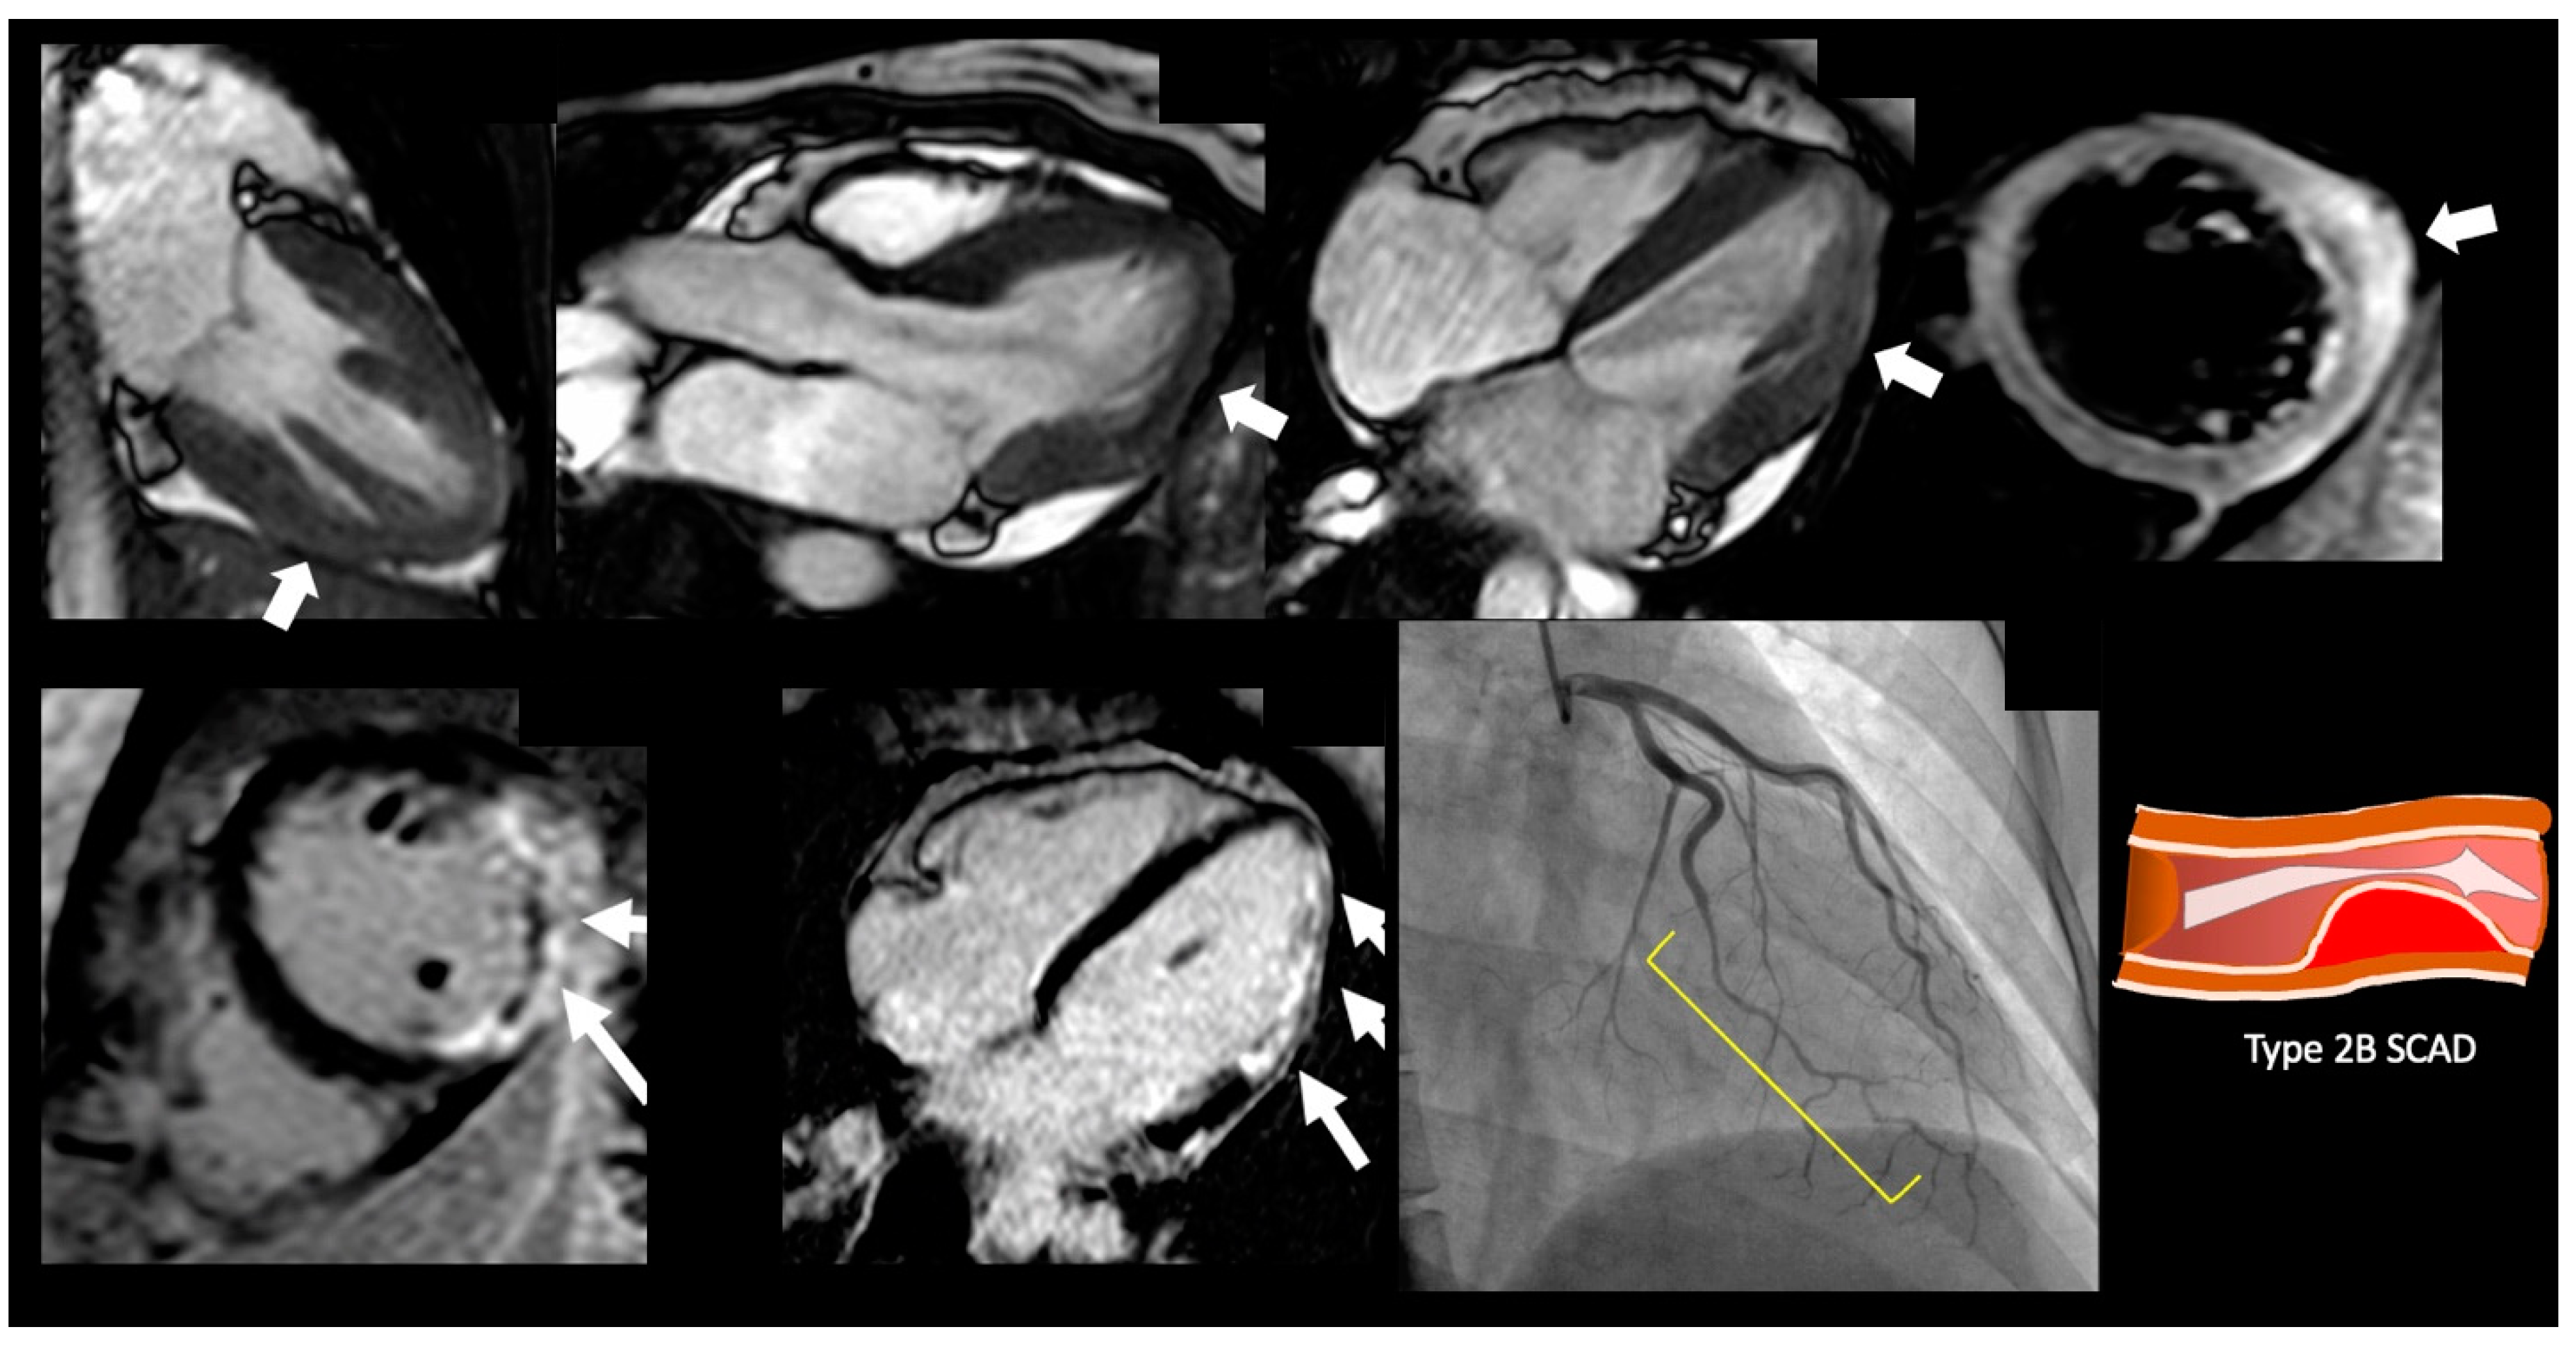

6. Acute MI